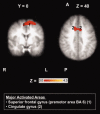

Understanding the underlying neural pathways that govern the highly complex neuromuscular action of swallowing is considered crucial in the process of correctly identifying and treating swallowing disorders. The aim of the present investigation was to identify the neural activations of the different components of deglutition in healthy young adults using functional magnetic resonance imaging (fMRI). Ten right-handed young healthy individuals were scanned in a 3-Tesla Siemens Allegra MRI scanner. Participants were visually cued for both a "Swallow" task and for component/control tasks ("Prepare to swallow", "Tap your tongue", and "Clear your throat") in a randomized order (event-related design). Behavioral interleaved gradient (BIG) methodology was used to address movement-related artifacts. Areas activated during each of the three component tasks enabled a partial differentiation of the neural localization for various components of the swallow. Areas that were more activated during throat clearing than other components included the posterior insula and small portions of the post- and pre-central gyri bilaterally. Tongue tapping showed higher activation in portions of the primary sensorimotor and premotor cortices and the parietal lobules. Planning did not show any areas that were more activated than in the other component tasks. When swallowing was compared with all other tasks, there was significantly more activation in the cerebellum, thalamus, cingulate gyrus, and all areas of the primary sensorimotor cortex bilaterally.